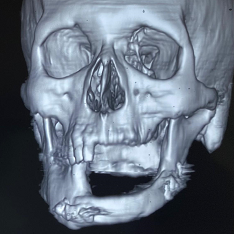

Microvascular Reconstruction

Bardhaman Maxillofacial Clinic: Your Trusted Partner in Microvascular Reconstruction.

Bardhaman Maxillofacial Clinic is a leading healthcare facility in Bardhaman, dedicated to providing comprehensive and specialized care for Microvascular Reconstruction. Our team of highly skilled and experienced maxillofacial surgeons is committed to delivering the highest quality treatment for a wide range of Microvascular Reconstruction treatment. Microvascular reconstruction is a highly specialized surgical technique that involves reconnecting tiny blood vessels. It is often used in reconstructive surgery to repair damage caused by trauma, cancer or birth defects.

During microvascular reconstruction, surgeons use microscopes and specialized instruments to reconnect blood vessels as small as a human hair. This allows for the transfer of tissue from one part of the body to another, such as using skin and muscle from the forearm to reconstruct a facial defect.

- Head and Neck Reconstruction: This technique is used to repair defects caused by cancer, trauma, or birth defects. It can involve reconstructing the jaw, nose, ear, or other facial features.